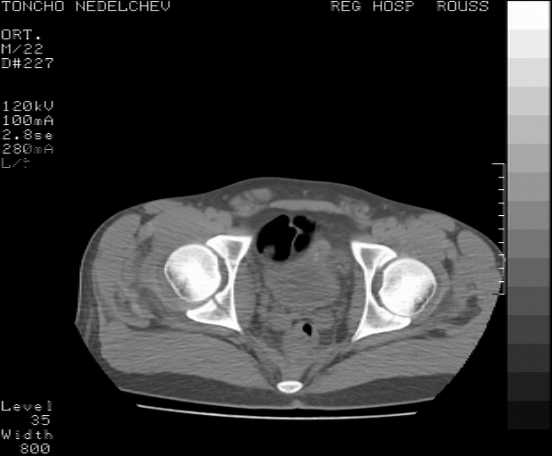

[Ortho] Acetabular fracture

Here are some more axial images. What is your opinion as for the timing of the operative treatment?